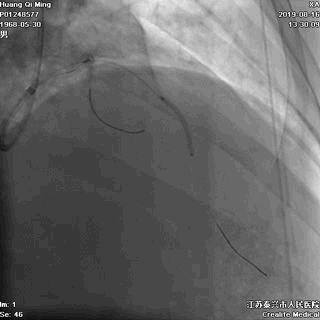

2.0*25 药物洗脱球囊,8atm*60秒释放药物

2.5*25 药物洗脱球囊,8atm*60秒释放药物